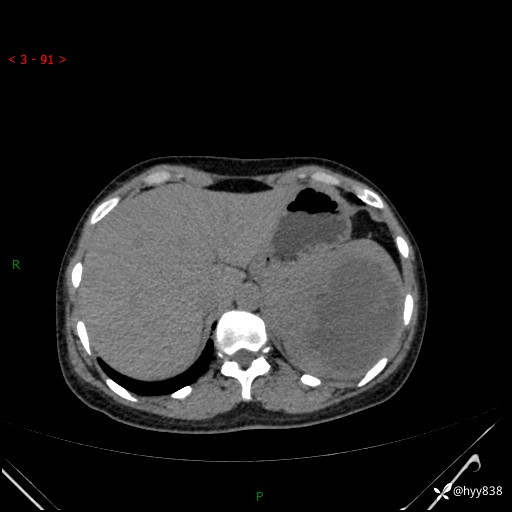

患者性别:男

患者年龄:44岁

主诉:外院超声发现脾脏占位,来我院进一步诊治。

临床诊断:脾脏占位

脾脏CT平扫+增强(动脉期+静脉期)